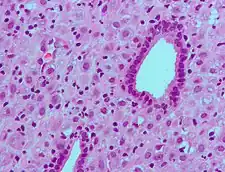

ESCs are the connective tissue cells of the endometrium that are fibroblastic in appearance. However, decidualization causes them to swell up and adopt an epithelial cell-like appearance due to the accumulation of glycogen and lipid droplets. Furthermore, they begin secreting cytokines, growth factors, and proteins like IGFBP1 and prolactin, along with extracellular matrix (ECM) proteins such as fibronectin and laminin. The increased production of these ECM proteins turns the endometrium into the dense structure known as the decidua, which produces factors that promote trophoblast attachment and inhibit overly aggressive invasion.[7]

The decidual reaction is seen in very early pregnancy in the generalized area where the blastocyst contacts the endometrial decidua. It consists of an increase in secretory functions of the endometrium at the area of implantation, as well as a surrounding stroma that becomes edematous.[8]

- Histopathology Uterus – Decidual reaction Microscopic review of decidualization